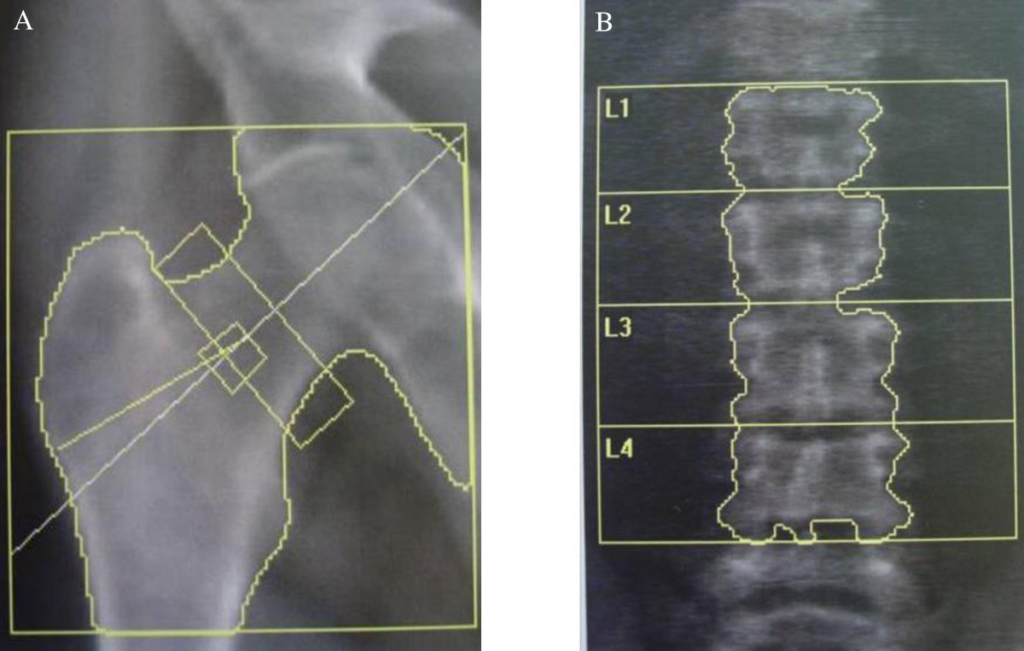

Scansione del femore prossimale

Per il femore, è essenziale indurre una rotazione interna dell’arto di circa 15-25 gradi utilizzando un apposito posizionatore per i piedi. Questa manovra serve a distendere il collo femorale, portandolo parallelo al piano di scansione e riducendo la sovrapposizione del grande trocantere.

Il piccolo trocantere deve essere minimamente visibile o assente in una scansione eseguita correttamente.

Le regioni di interesse (ROI) diagnostiche sono il “collo femorale” (Femoral Neck) e il “femore totale” (Total Hip). Il valore di BMD più basso tra i due deve essere utilizzato per la classificazione densitometrica.

L’area di Ward non deve essere usata per la diagnosi a causa della sua elevata variabilità e piccola dimensione.